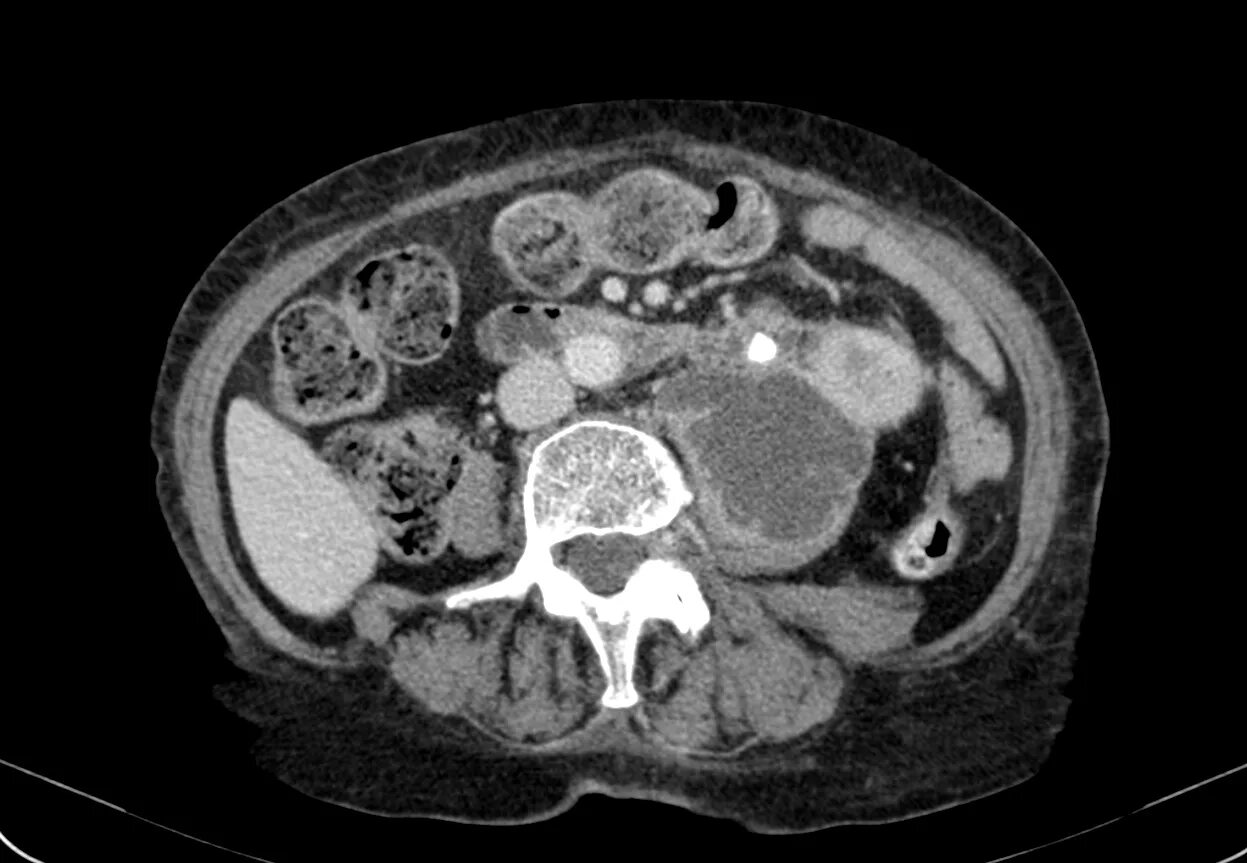

Пиелонефрит кт